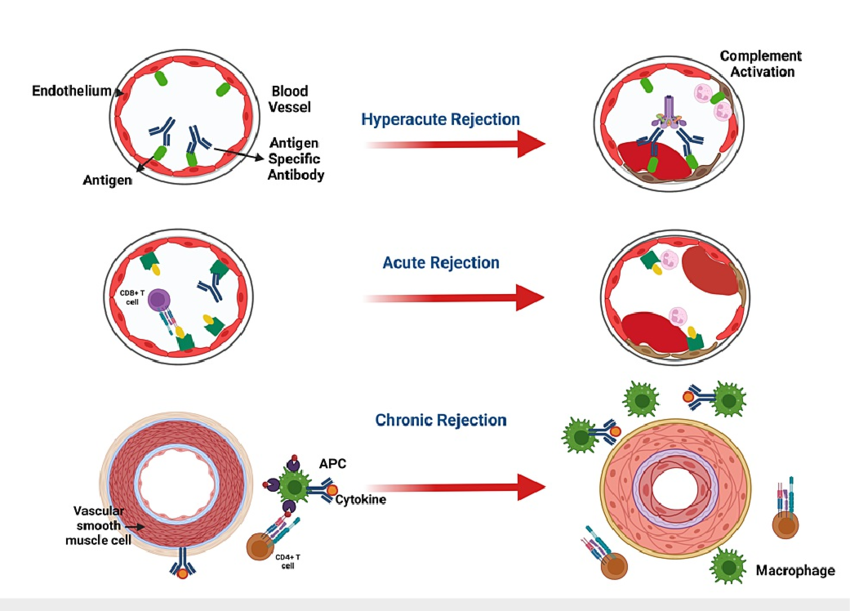

Xenotransplantation is a constant battle against the immune system. The body’s reaction to a pig organ typically follows a sequence:

Types of Graft Rejection

Hyperacute and Acute Rejection

In early attempts, the immune system would destroy pig organs within minutes to hours via hyperacute rejection. This happened because:

- Human antibodies bound to pig‑specific antigens.

- The complement system activation, causing massive blood‑clotting and organ destruction.

Modern gene editing and immunosuppression have reduced the incidence dramatically, but low‑level immune activity often still occurs over days to months.

Chronic Immune Reactions

Even with genetic modifications, the human immune system continues to interact with the pig graft in the long run.

A 2026 immunology paper analyzing the first long‑lasting pig‑kidney xenograft showed that:

- Certain immune‑cell subsets remained active even months after transplant.

- Gene‑expression patterns in the graft revealed subtle changes reflective of ongoing immune stress.